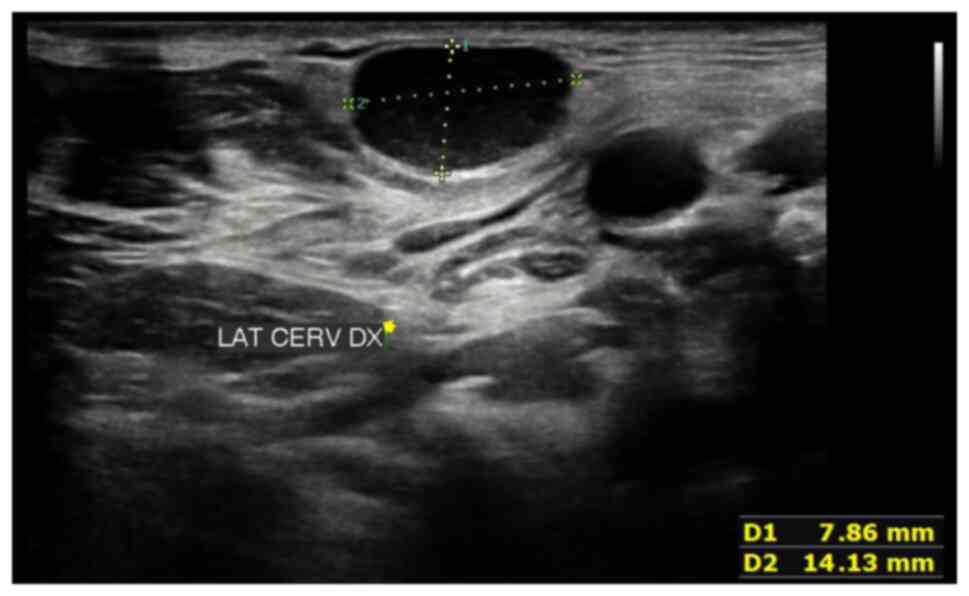

Following a neck ultrasound which revealed enlarged lymph nodes, a subsequent computed tomography scan confirmed these findings in the bilateral laterocervical regions, as well as in multiple mesenteric, external iliac and para-aortic locations (Fig. 1). PET/CT imaging indicated significant metabolic activity with abnormal tracer accumulation in various lymph node regions and nodules in the mesenteric area.

Figure 1

Neck ultrasound illustrating enlarged lymph nodes.